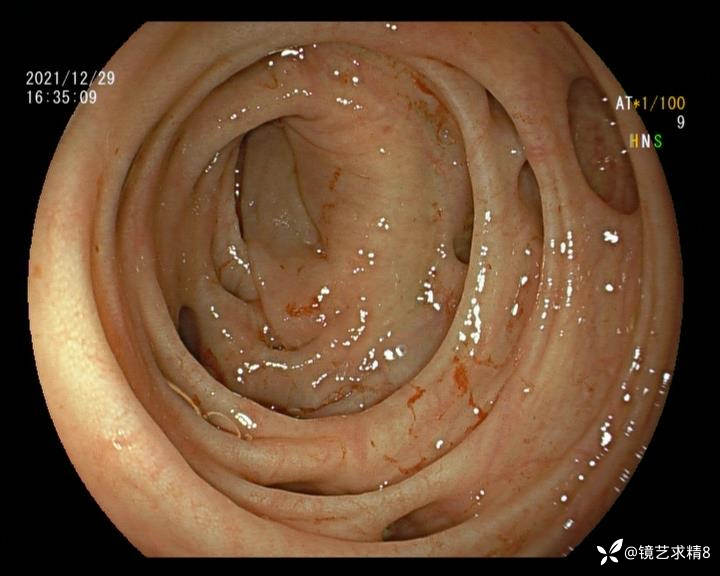

结肠内违建⥤结肠多发憩室☞续

小壮兵爱学习等 2人推荐看到手机存有2年前一个病例仅有的3张图片,因为没有更多的图片就只描述了多发憩室这个内容,没想到浏览量很快上万,很多都和我一样第一次见这么多憩室的结肠,就不得不想要把2年前所有的片子拷贝出来分享。该病例憩室合并外源性因素成为憩室出血的原因。后面附有代表性的全结肠图片。

患者以消化道出血入院,胃镜未见异常,肠镜进入乙状结肠就看到很多憩室,同时还看到肠腔用清肠药后移动下来1枚尖锐的枣核,这么多憩室,这个枣核扎入憩室的机会非常大,推测应该是掉入一坑🕳就算出来还会有很多坑🕳🕳🕳等着,掉入憩室内很容易刺破血管,这可能就是消化道出血的原因,继续前进可以看到有一些憩室内翻,还有一些息肉,问题来了,那么多憩室,犯罪分子是抓住了,它在那些憩室内作过案?到达回盲部后挨个冲洗,但憩室大小又不足以把镜头进入憩室内观察,针对有血块的憩室冲洗后可疑出血的以夹子闭合或套扎,取出枣核,如果有锥形透明帽可能钻入憩室精准电凝效果更好,若内镜下操作失败介入治疗成功率更高,经内镜下治疗后观察未再出血出院。